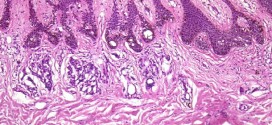

El cáncer epidermoide de esófago. Tumor maligno en general y especialmente formado por células epiteliales. El cáncer epidermoide de esófago es una enfermedad por la que se forman células malignas (cancerosas) en los tejidos del esófago. El esófago es el tubo hueco, muscular que transporta los alimentos y los líquidos desde la garganta al estómago. La pared del esófago comprende …